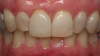

Once the laboratory receives the impression and instructions regarding abutment selection, restoration design/type, and desired shades, the impressions are scanned and/or otherwise used for fabricating the implant-supported restoration and abutment. This includes creating models to verify fit and contacts (Figure 21). If a screw-retained restoration is selected, software is used to calculate and determine the proper angulation of the screw channel, and the restoration and abutment are fabricated to offset that to the cingulum. In the case of the female patient who presented with the missing tooth No. 8, the restoration was fabricated and placed to be a mirror image of the adjacent natural tooth, with proper soft-tissue architecture (Figure 22).

Fig 22. In the present case of the patient missing tooth No. 8, the final restoration represented a mirror image of the adjacent natural tooth, with proper soft-tissue architecture.

Figure 22